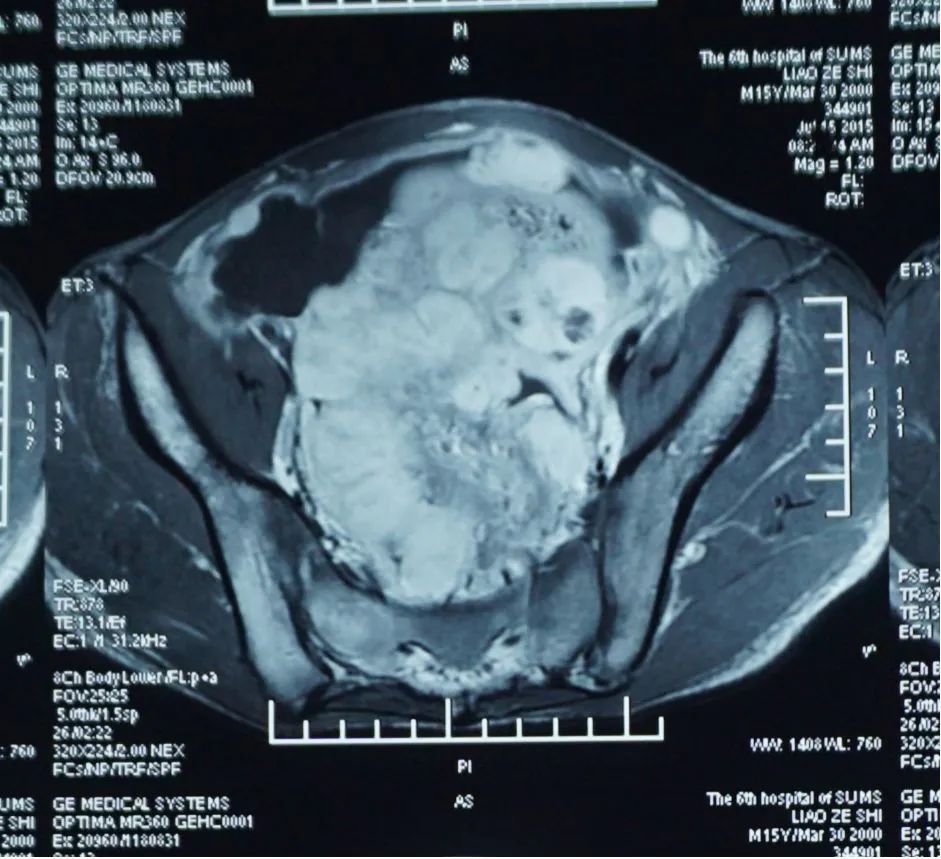

廖某,男,15岁。发现腹腔、盆腔多发肿块1月余。2015年7月29日入院。

2015-6月起患者无明显诱因出现持续腹泻,每日大便约10-20次,呈水样便,伴腹胀。当地医院CT:中下腹及盆腔多发肿物;肿物穿刺活检:上皮样炎性肌纤维母细胞瘤。

腹、盆腔炎症肌纤维母细胞瘤(Ⅳ期)

克唑替尼口服3日后,患儿腹部肿块逐渐缩小至4cm*3cm;口服第6天,腹部较前变软,未再排血便,神智较前转清,对答切题。体查:三凹征(-)中下腹部包块3cm*3cm。口服克唑替尼后第12天,患儿无胸水流出,能自行进食,腹部肿块缩小至2cm*2cm,患儿出院。患儿不规律口服克唑替尼一个月后,自行停药。复查腹部CT:腹腔大网膜肿块,互相融合,最大约7.1cm*4.7cm,较初诊外院片缩小。

起病时

停口服药治疗后3个月